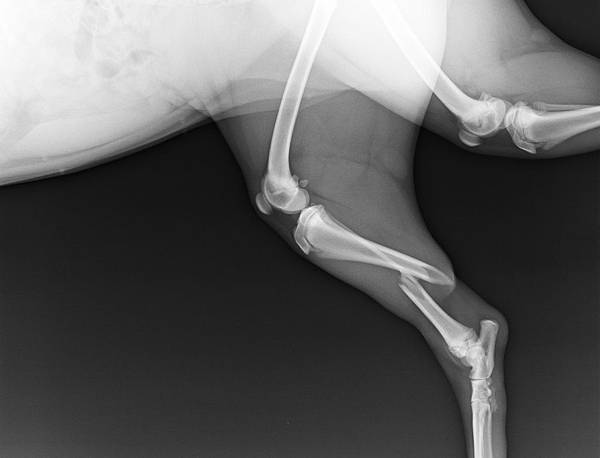

妞妞是今天下午好心人送來治療骨折問題的小黑狗

好心人也願意在手術後收養他

小譚醫師實在太開心聽到這樣的好事情

決定加班幫妞妞修理好腳腳